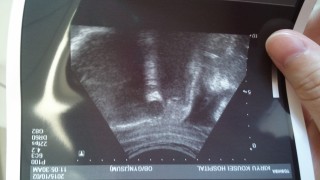

写真:32w6d:イクラちゃんママさん:2130g

2130グラム。頭囲は8.9センチ。少し頭が大きいかな?この2週間で560グラムも大きくなりました。順調に育っています。 ぷっくりタラコくちびるが彼にそっくり。